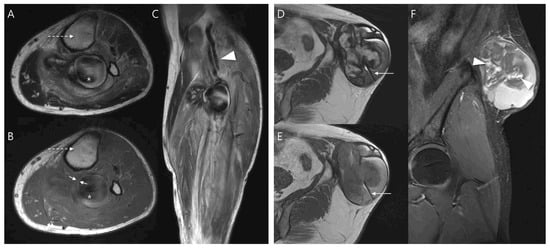

Pseudoaneurysm Versus Chronic Expanding Hematoma on MRI: Hematoma-like Lesions with Distinct Therapeutic Strategies

by

Seul Ki Lee, Jun-Ho Kim and Jee-Young Kim

Biomedicines 2025, 13(11), 2834; https://doi.org/10.3390/biomedicines13112834 - 20 Nov 2025

Background/Objectives: Pseudoaneurysm and chronic expanding hematoma (CEH) are uncommon soft tissue lesions that can mimic hematoma or hemorrhagic tumors on magnetic resonance imaging (MRI). Because treatment strategies differ, accurate differentiation is important. This study aimed to compare MRI characteristics of pseudoaneurysm and CEH

Background/Objectives: Pseudoaneurysm and chronic expanding hematoma (CEH) are uncommon soft tissue lesions that can mimic hematoma or hemorrhagic tumors on magnetic resonance imaging (MRI). Because treatment strategies differ, accurate differentiation is important. This study aimed to compare MRI characteristics of pseudoaneurysm and CEH and identify distinguishing imaging features. Methods: We retrospectively reviewed 12 patients diagnosed between June 2010 and June 2023 with pseudoaneurysm (n = 6) or CEH (n = 6). Patient demographics, lesion depth, and size were compared. MRI features were evaluated for morphology, internal characteristics, pulsatile artifact, and involvement of adjacent structures. Results: Pseudoaneurysms were consistently located in the muscle layer, whereas CEHs were predominantly found in the subcutaneous fat layer (83.3%, p = 0.015). CEHs were significantly larger than pseudoaneurysms (13.5 ± 3.9 cm vs. 6.1 ± 3.3 cm, p = 0.005). Pseudoaneurysm more frequently exhibited ovoid morphology (100%), central flow void on T1WI and T2WI (100%), inner peripheral high SI on T1WI (83.3%), and neurovascular bundle involvement (100%) (all p < 0.05), while CEHs demonstrated multilobular morphology (100%) and internal septations (83.3%) (p < 0.05). Conclusions: Lesion location, size, morphology, central flow void, inner peripheral high T1 signal, septation, and neurovascular involvement enables reliable MRI differentiation between pseudoaneurysm and CEH, guiding accurate diagnosis and guiding appropriate management.